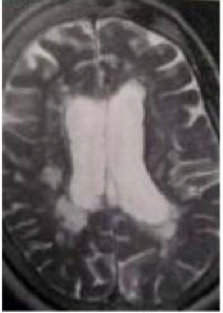

Perhatikan gambar, diagnosis manakh yang paling mungkin?

A. Penyakit metastasis

B. Sklerosis Majemuk

C. Infark Lakuna Majemuk

D. Penyakit Canavan

E. Penyakit Alexander

B